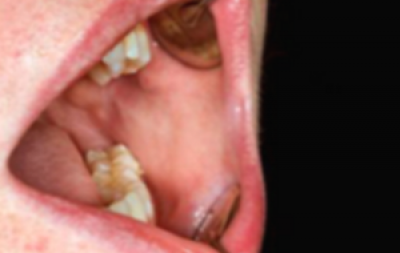

Gezwel

Een zwelling (weefsel surplus) die niet verklaard kan worden (bijvoorbeeld trauma aan gebit of door kunstgebit) moet ook als mogelijk verdacht voor kanker worden beschouwd, Het kan een exofytisch weefselgezwel zijn dat een knobbel veroorzaakt met een glad, lobvormig of geplooid oppervlak (figuur 8). Zwamvormige gezwellen komen voor, als gevolg van centrale necrose van een snel groeiende massa die sneller groeit dan de bloedvoorziening kan ondersteunen (figuur 9).

vlieszwelling met een gespikkeld aanzien vóór de tumor.